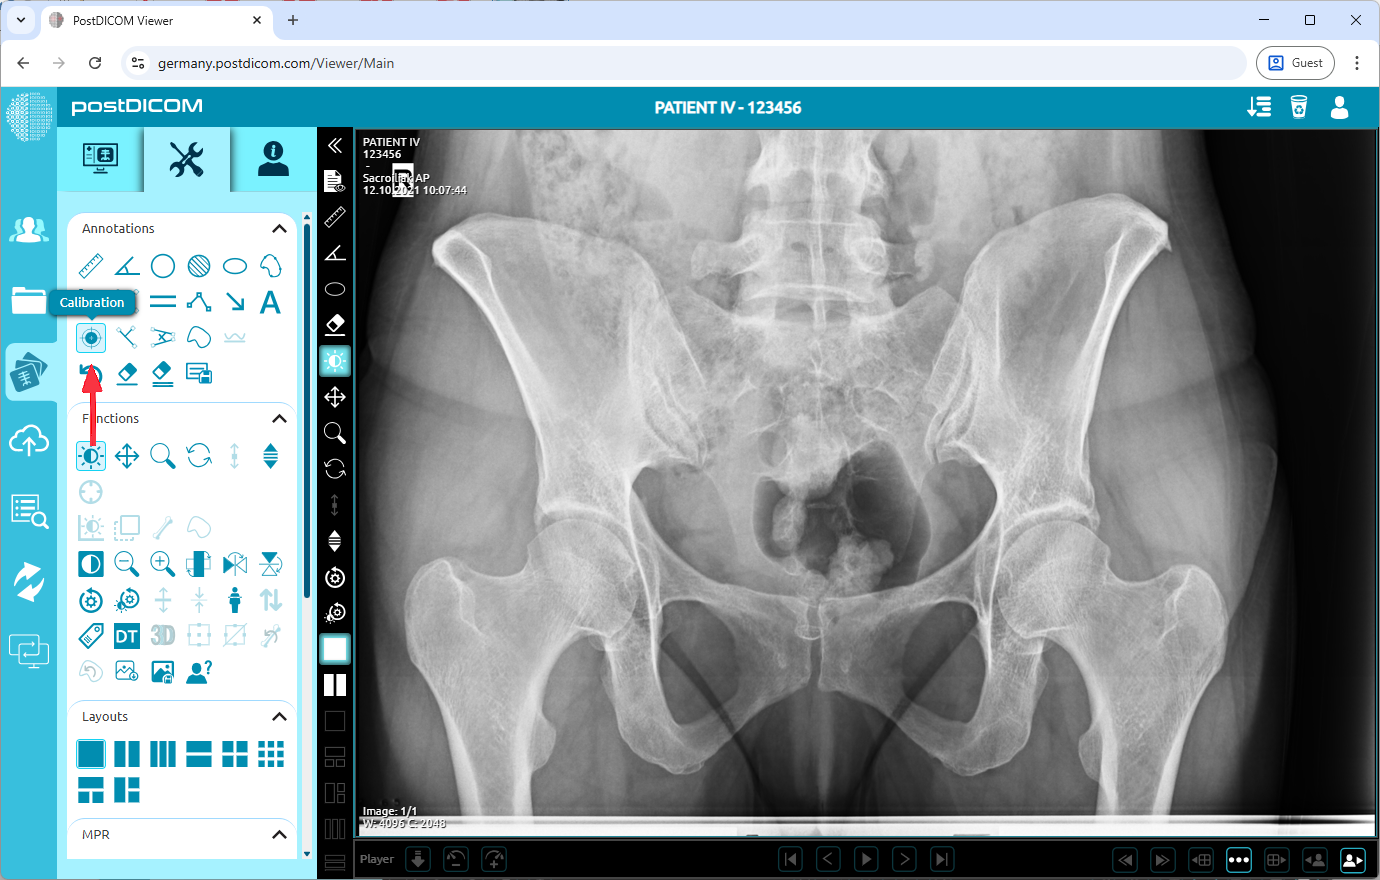

After you have clicked, the tools section will be displayed. In the “Annotations” field, click on the “Calibration” icon on the upper left side of the section.